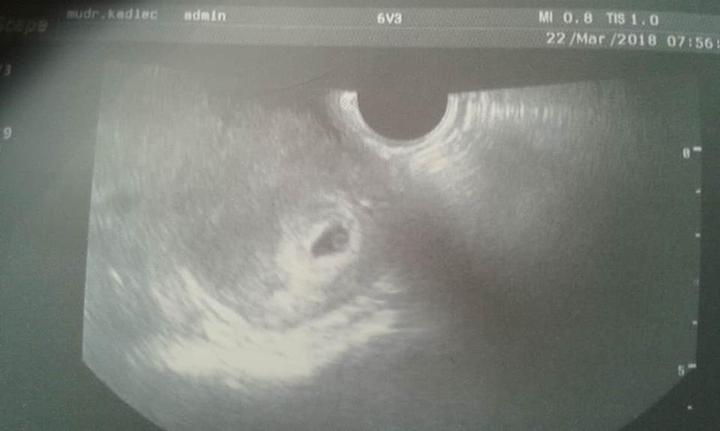

Jak už jsem předeslala v minulém díle, po proběhlém potratu k nám zavítalo nové miminko.

Přesto to nebylo úplně lehké a bez komplikací...

V šestinedělí dorazila moje první popotratová menstruace, která trvala skoro 14 dní, no a po konci šestinedělí na kontrole u doktora vše ok.

Zítra ráno mě čeká kontrolní utz, od začátku těhu stále špiním, a před pár dny bylo i slabé krvácení, tak mám už teď strach i obavy, jak to dopadne. V lednu jsem měla potrat( anembryomola)takže teď je to prostě takový celý opravdu o čekání a trpělivosti. Vím, že musím myslet pozitivně, a věřit... A věřím! Ale jako bych si bála se připouštět, občas, že jsem vůbec těhotná, aby potom ta bolest nebyla třeba taková, jako když se na tohle těhotenství upnu..nevím, zda mě chápate a měla jste to některá taky tak v těhotenství po potratu..Jak jste to zvládali psychicky a jak jste se k tomu stavěli? obzvlášť , pokud byli ještě i navíc nějaké komplikace(špinění atd.)

až ke konci mi brali krev(plod stále nebyl vidět-jen prázdný gestační váček)na porovnání...měla jsem tehdy ve středu 16 000 a v pátek 24 000, takže jim už bylo jasný, že je to blbý:-/

Nyní jsem byla na krvi v 4+2 a byla 124 a v 4+4 391,92...takže hcg roste krásně, oproti minule..

Byl to od počátku prostě jeden velký stres, nechat si dítě, nebo ne, potom jsme se rozhodli , že ano, a věřte mi, že pro mě, jako pro mámu tří dětí to bylo snad nejhorší období v mém životě. A i když by to bylo chlapovo první dítě, byl z toho tak mimo, že si prostě na tu myšlenku, že bude tátou, musel zvykat asi ho to stálo hodně sil..ale i když už se s tím zázrakem smířil, a začal se možná už i těšit, začala jsem špinit i před utrogestan, co jsem užívala a po několika kontrolách, utz a odběrech se potvrdilo, že miminko se přestalo vyvýjet hned někdy na začátku a rostl jen prázdný váček, bez žloutkového a bez embrya.

V lednu jsem potratilav 7tt(potrat vyvolaný tabletami)protože se mimi nevyvíjelo..rostl jen prázdný gestační váček, brala jsem utrogestan i když jsem neměla špinění, ani krvácení, ale i přes užívání jsem po 14 dnech začala špinit..a potvrdila se diagnoza.Krev mi brali na porovnání až týden před verdiktem, a už bylo jasno:-/že se nezdvojnásobuje jak by mělo...

Nyní jsem těhotná..a stejně i jako v minulém těhu jsem týden před ms slabě krvácela sem tam, skoro týden..po pozitivním testu (duch den před ms)jsem volala dr.co dál, na utz by stejně nc neviděl, a doporučil mi brát utrogestan, že by měl pomoci s tím občasným slabým zakrvácením.

Tak aby toho všeho nebylo málo, dnes na kontrolním utz se po čtvrtečních podaných tabletách na vypuzení nevyvíjejícího miminka přišlo na to, že sice gestační váček je pryč, a těhotenské tkáně asi taky,ale napsali mi do zprávy v děloze nehomogenní obsah nejvýše do 15 mm...

Píchli mi injekci methylerdometrinu a dali kapky Cornutamin(3xdenně 30 kapek)

Za týden kontrolní utz a když tam bude pořád krev, jdu na revizi...ach jo☹